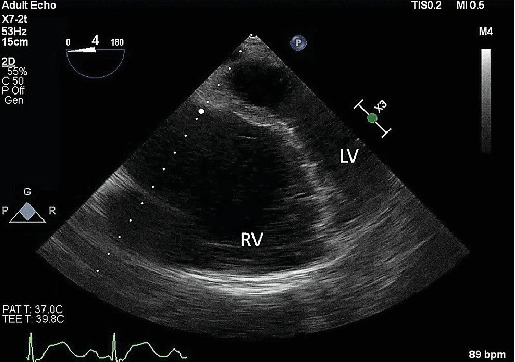

Abstract Image